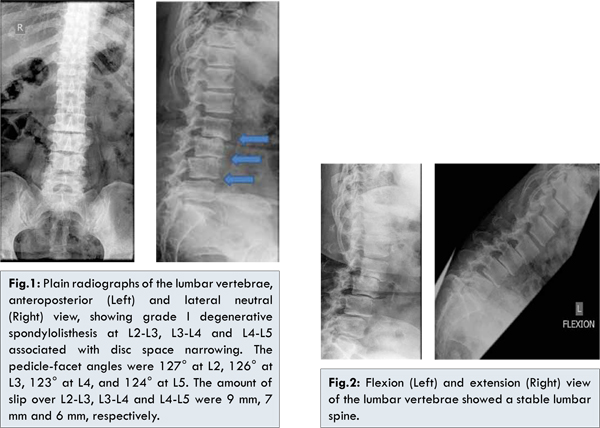

This 58 year old female presented with 4 year history of low back pain that progressively worsen over the past 1 year and was associated with bilateral buttock, lateral thigh and calf pain along L4 and L5 dermatome.  Pain was increased upon walking and relieved by rest. Claudication distance measured 5-10 meters. Physical examination revealed tenderness over the lumbar spine. Lumbar flexion and extension were limited and painful. There was weakness of the bilateral extensor hallucis longus (i.e. muscle strength grading of 4/5) and sensation at L4 and L5 dermatome was reduced. Plain radiography of the lumbar vertebrae revealed grade I degenerative spondylolisthesis at L2-L3, L3-L4 and L4-L5 [Fig.1,2]. Radiological studies showed elevated pedicle-facet angle and W- type of facet joints from L2-L5. Magnetic resonance imaging revealed showed severe multilevel spinal canal stenosis from L2-S1 [Fig.3].